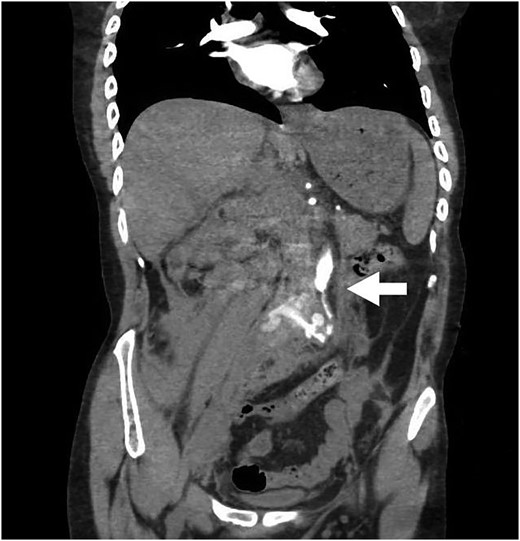

Our patient is a 24-year-old male with the EDS type VI who had undergone rod fixation of his spine for scoliosis, ocular surgery for a ruptured globe and ligation of his popliteal artery after an attempt was made to repair his aneurysm. The patient was being followed at Duke EDS Clinic where he underwent an extensive workup, and a definitive diagnosis was established. He presented to the emergency room (ER) after being kicked in the abdomen during a martial arts class. The patient felt an instant abdominal pain which resolved quickly. The patient went home after the incident and then developed nausea, vomiting and diaphoresis. He was hemodynamically normal in the ER. His groin pulses were slightly diminished compared with his radial pulses. The patient underwent a computed tomography (CT) scan of the chest, abdomen and pelvis with intravenous contrast. The patient was found to have traumatic aortic injury (Fig. 1). Cardiovascular surgery was consulted. The patient was admitted to the ICU for nonoperative therapy. He was started on Esmolol intravenously, and Diltiazem was added in order to keep his mean arterial pressure around 60. After 2 days in the ICU, the patient was transitioned to medications by mouth. He was allowed to ambulate on the fourth day and discharged on the eighth day after a long discussion with him and his family.